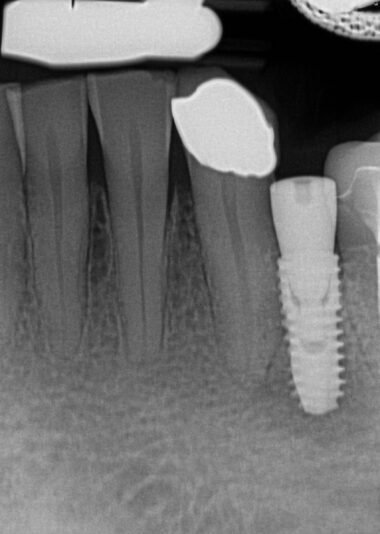

Hi, this implant was placed in June 2024. I have 3PAs (one from day of placement, one month later, and 9 month later). The intraoral picture of the soft tissue is from yesterday and tissue looks great… patient has no discomfort/pain either. She did have some discomfort between 2-3rd week after placement but subsided after taking antibiotics. On the one month xray, I may have missed the radioluency starting in apical 1/3.

Yesterday, I tapped the HA with the end of my mirror and wiggled the implant with no pain nor any perceptible movement. I am very suspicious, of course, about the radiolucency surrounding the apical 1/2 of the implant and am almost certain that the implant has failed (right?). I have removed failed implants at about 4 weeks (came out easily since still has not osseointegrated) but not at 9 months out…